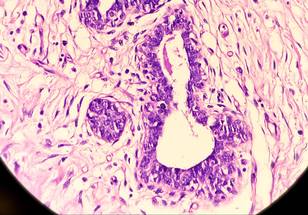

The University of Cincinnati's Robert Van Haren was featured in a MedCentral article discussing recent research that found smoking cessation significantly reduced the risk of developing hidradenitis suppurativa, a non-contagious chronic inflammatory skin disorder characterized by painful nodules, abscesses and scarring.

Van Haren and Kuhr said cigarette smoke contains many harmful chemicals that can trigger our bodies to produce inflammatory signals, which in some cases can lead to hidradenitis suppurativa.